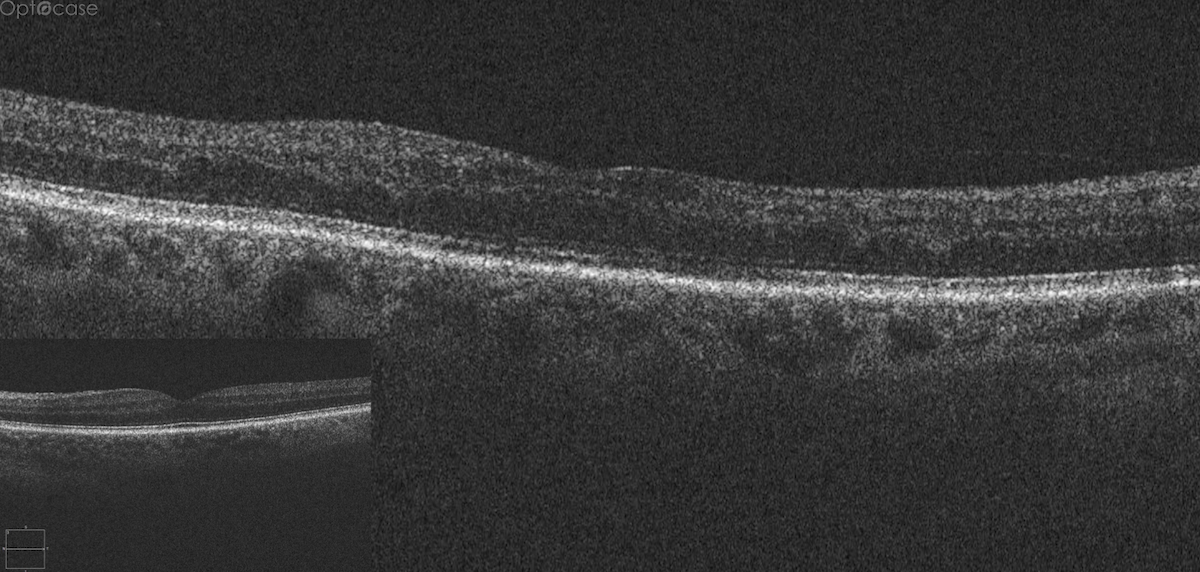

A 73-year-old presents with new distortion. Why?

Here there is loss of the regular macular depression. There is a bright line present on the surface of the retina. In addition, there is separation of the retinal layers in the inner retina.

The patient was diagnosed with a schisis secondary to an epiretinal membrane. This complication is seen in over 50% of ERMs (video).